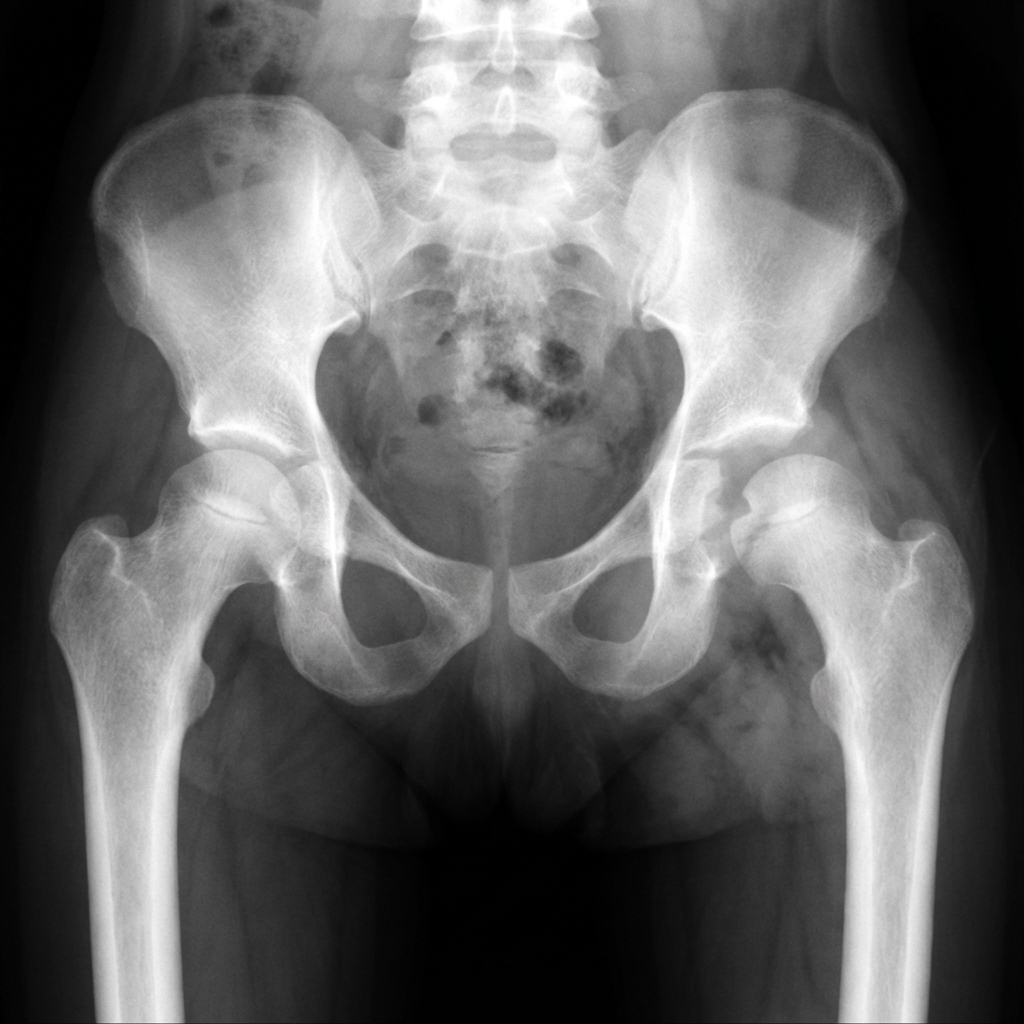

AP pelvis radiograph of a 2-year-old child demonstrating left hip septic arthritis. The left hip joint space is widened compared to the right. There is lateral subluxation of the femoral head with disruption of Shenton's line. Soft tissue swelling is visible around the hip. No bony changes yet (early presentation). The constellation of findings suggests septic arthritis with effusion requiring urgent intervention.